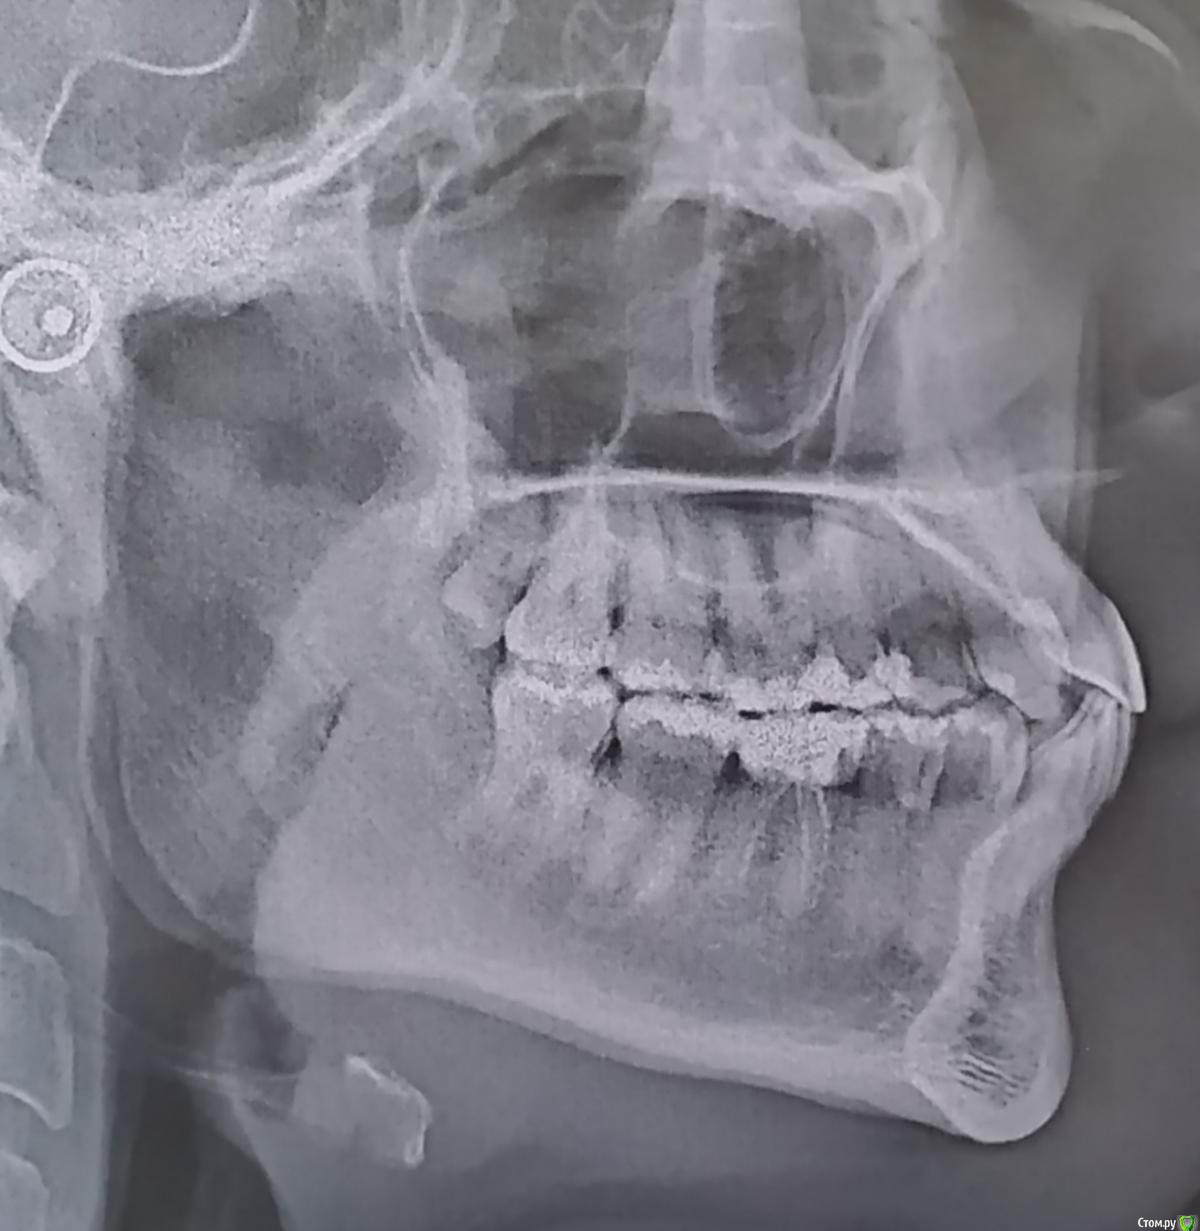

Все началось с того, что в 10 лет я поняла, что при улыбке у меня не поднимается верхняя губа и верхние зубы не видно, ну может на 1 мм. Так я ходила 20 лет с комплексом улыбки. А в 30, попав к новому стоматологу, врач предложила мне сделать художественные реставрации и удлинить верхние зубы. И тут началось.

Нельзя удлинить левый верхний, потому что нижние пошли а наклон, и он упирается в левый нижний.

3 сказала, что с прикусом все ок, вот только передние 4 немного кривые, но задвинуть их нет возможности, потому что все плотно после появления восьмерок и бонусом одной 9-ки.

Первые три врача смотрели меня без снимков.

4, посмотрев мои снимки, сказала, что на вид все просто, но если начинать просчеты, то не все так просто. И в моем случае система Invisalign лучшее решение. Она очень много всего рассказала, долго писать, но ее мнение понравилось больше всего. Проблема только в том, что капы носить два года, а у меня сейчас есть ночная от бруксизма и я постоянно на утро просипаюсь с болями в животе от того, что во рту что-то есть и сильное слюноотделение.